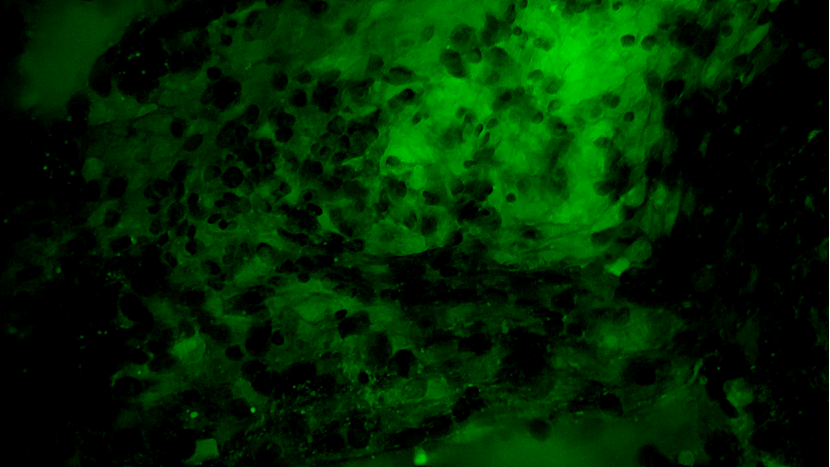

術(shù)中EndoSCell?細胞圖像如下:

可疑組織的腫瘤細胞殘留:細胞核異型性顯著,分布密集且不規(guī)則